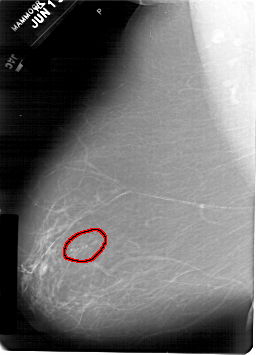

FILE: A_1934_1.LEFT_MLO.OVERLAY

TOTAL_ABNORMALITIES 1

ABNORMALITY 1

LESION_TYPE CALCIFICATION TYPE AMORPHOUS DISTRIBUTION CLUSTERED

ASSESSMENT 3

SUBTLETY 4

PATHOLOGY BENIGN

TOTAL_OUTLINES 1

BOUNDARY